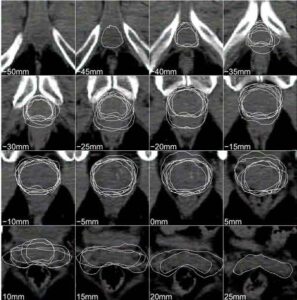

Prime conferme ufficiali sull’efficacia della radioterapia intraoperatoria, mentre un anticorpo monoclonale porta a destinazione un potentissimo chemioterapico (altro…)